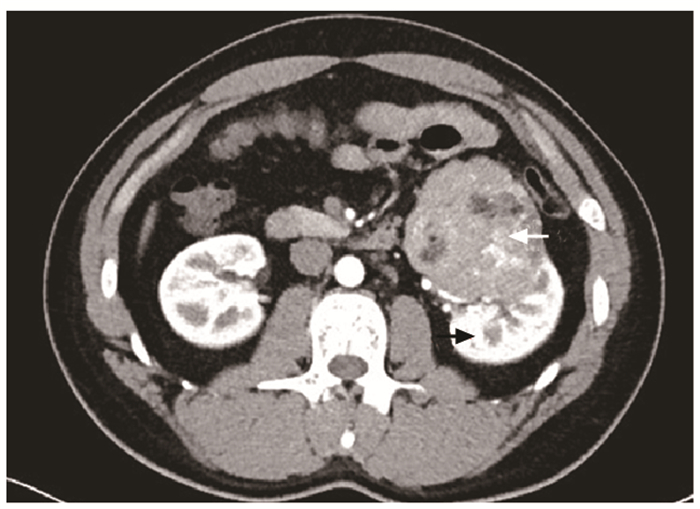

结果   14例AML患者中有1例相对孤立肾合并AML、7例多发AML、8例巨大AML(肿瘤最大直径>7 cm)、6例紧邻肾集合系统或肾门的AML以及2例合并出血破裂史AML, 病情复杂, 手术难度大。采取经腹腔镜或开放肾部分切除或肿瘤剜除术后, 顺利切除肿瘤, 病理检查提示肾AML, 术后定期门诊随访, 行CT扫描均无复发。全部患者术后肾功能保持良好, 术前和术后1个月血肌酐水平分别为(84.1±26.8)μg/ml和(97.5±37.0)μg/ml, 两组数据差异无统计学意义(t=-3.193, P>0.05)。

Results  Among 14 patients with renal AML, 1 had a relative solitary kidney with AML, 7 had multiple AML, 8 had huge AML (the maximum diameter of the tumor >7 cm), 6 had AML adjacent to the renal collection system or the renal portal, and 2 had AML combined with bleeding and rupture history; all cases were complicated and difficult to treat. All operations were successfully performed by laparoscopic or open partial nephrectomy or enucleation of the tumor, and pathological examination indicated renal AML. All patients were regularly followed up and no recurrence was found by CT scanning. The renal function of all patients was well preserved; the concentration of serum creatinine before and 1 month after the operation were (84.1±26.8)μg/ml and (97.5±37.0)μg/ml respectively, without statistically insignificant difference (t=-3.193, P>0.05).